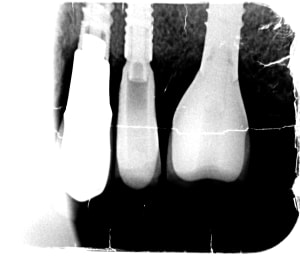

Mise en Charge Immédiate POSITDENTAL 015.jpg